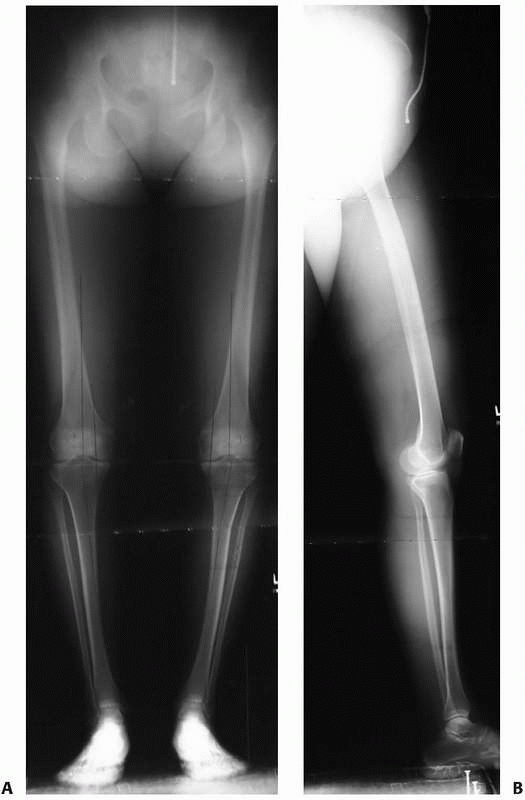

Anteroposterior (AP) and lateral radiographs of the involved bone,

equivalent accuracy.88,92,99 Bilateral

AP and lateral 51-inch alignment radiographs are obtained for lower extremity deformities to evaluate limb alignment (Fig. 26-2). Flexion/extension lateral radiographs may be useful to determine the arc of motion of the surrounding joints.

FIGURE 26-2 A. Bilateral weight-bearing 51-inch AP alignment radiograph and (B) a 51-inch lateral alignment radiograph, which are used to evaluate lower extremity limb alignment.